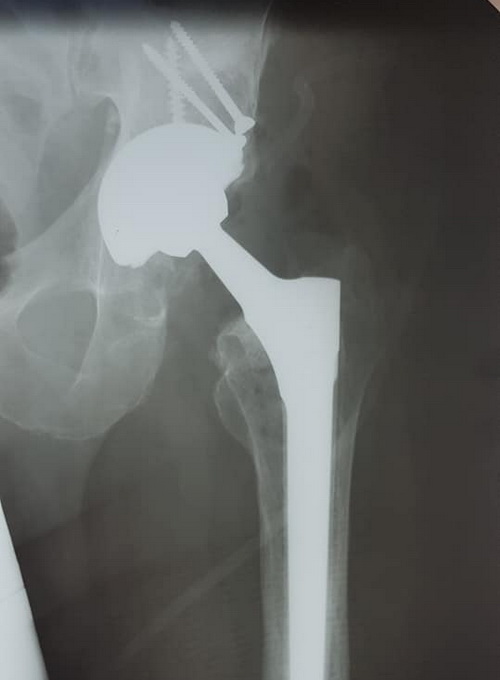

Хворий М. 37 років. Діагноз: псевдоартроз лівої кульшової западини, стан після МОС з наявністю фіксаторів...